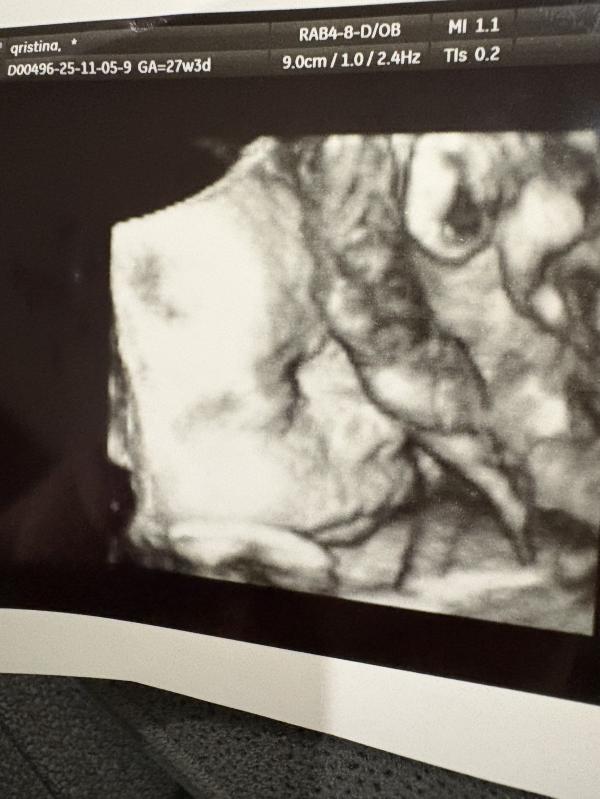

27 недель беременности: размеры малыша и наши переживания

Я влюбилась в эту булочку 🥹

27 недель, около 1100г, но по см отстает на дня 4, но и мы небольшие с мужем 🥰